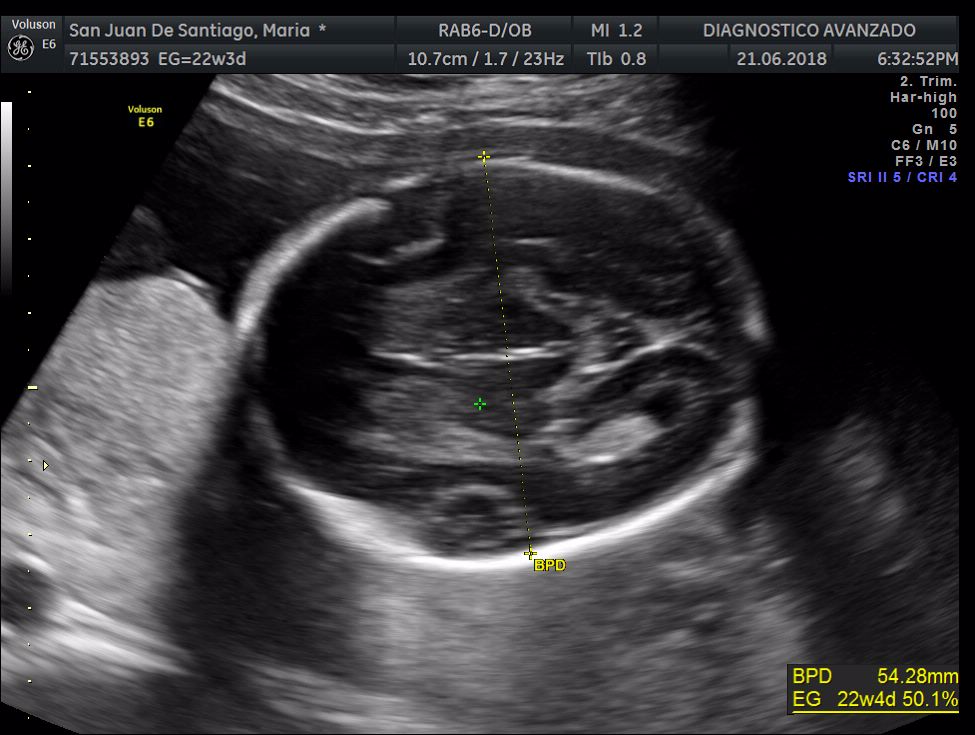

¡Hola a todos! Hoy hemos ido a hacer la tradicional ecografía 3D de la niña, os dejamos todo el material (aunque es un poco demasiado).